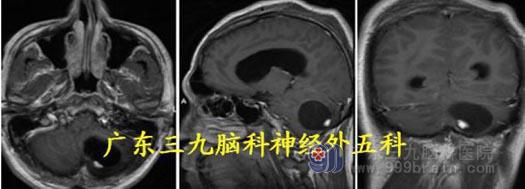

见近窦汇小脑蚓部、左小脑半球有部分肿瘤裸露,肿瘤呈囊实性,打开囊壁,吸除淡黄色囊液,见两个灰褐色瘤结节位于左侧小脑半球,质软、血管丰富并杂乱生长、无包膜,边界较清,显微镜下分块全切除肿瘤。

术后头颅MR 显示肿瘤完整切除。病理:血管母细胞瘤,WHO I 级。